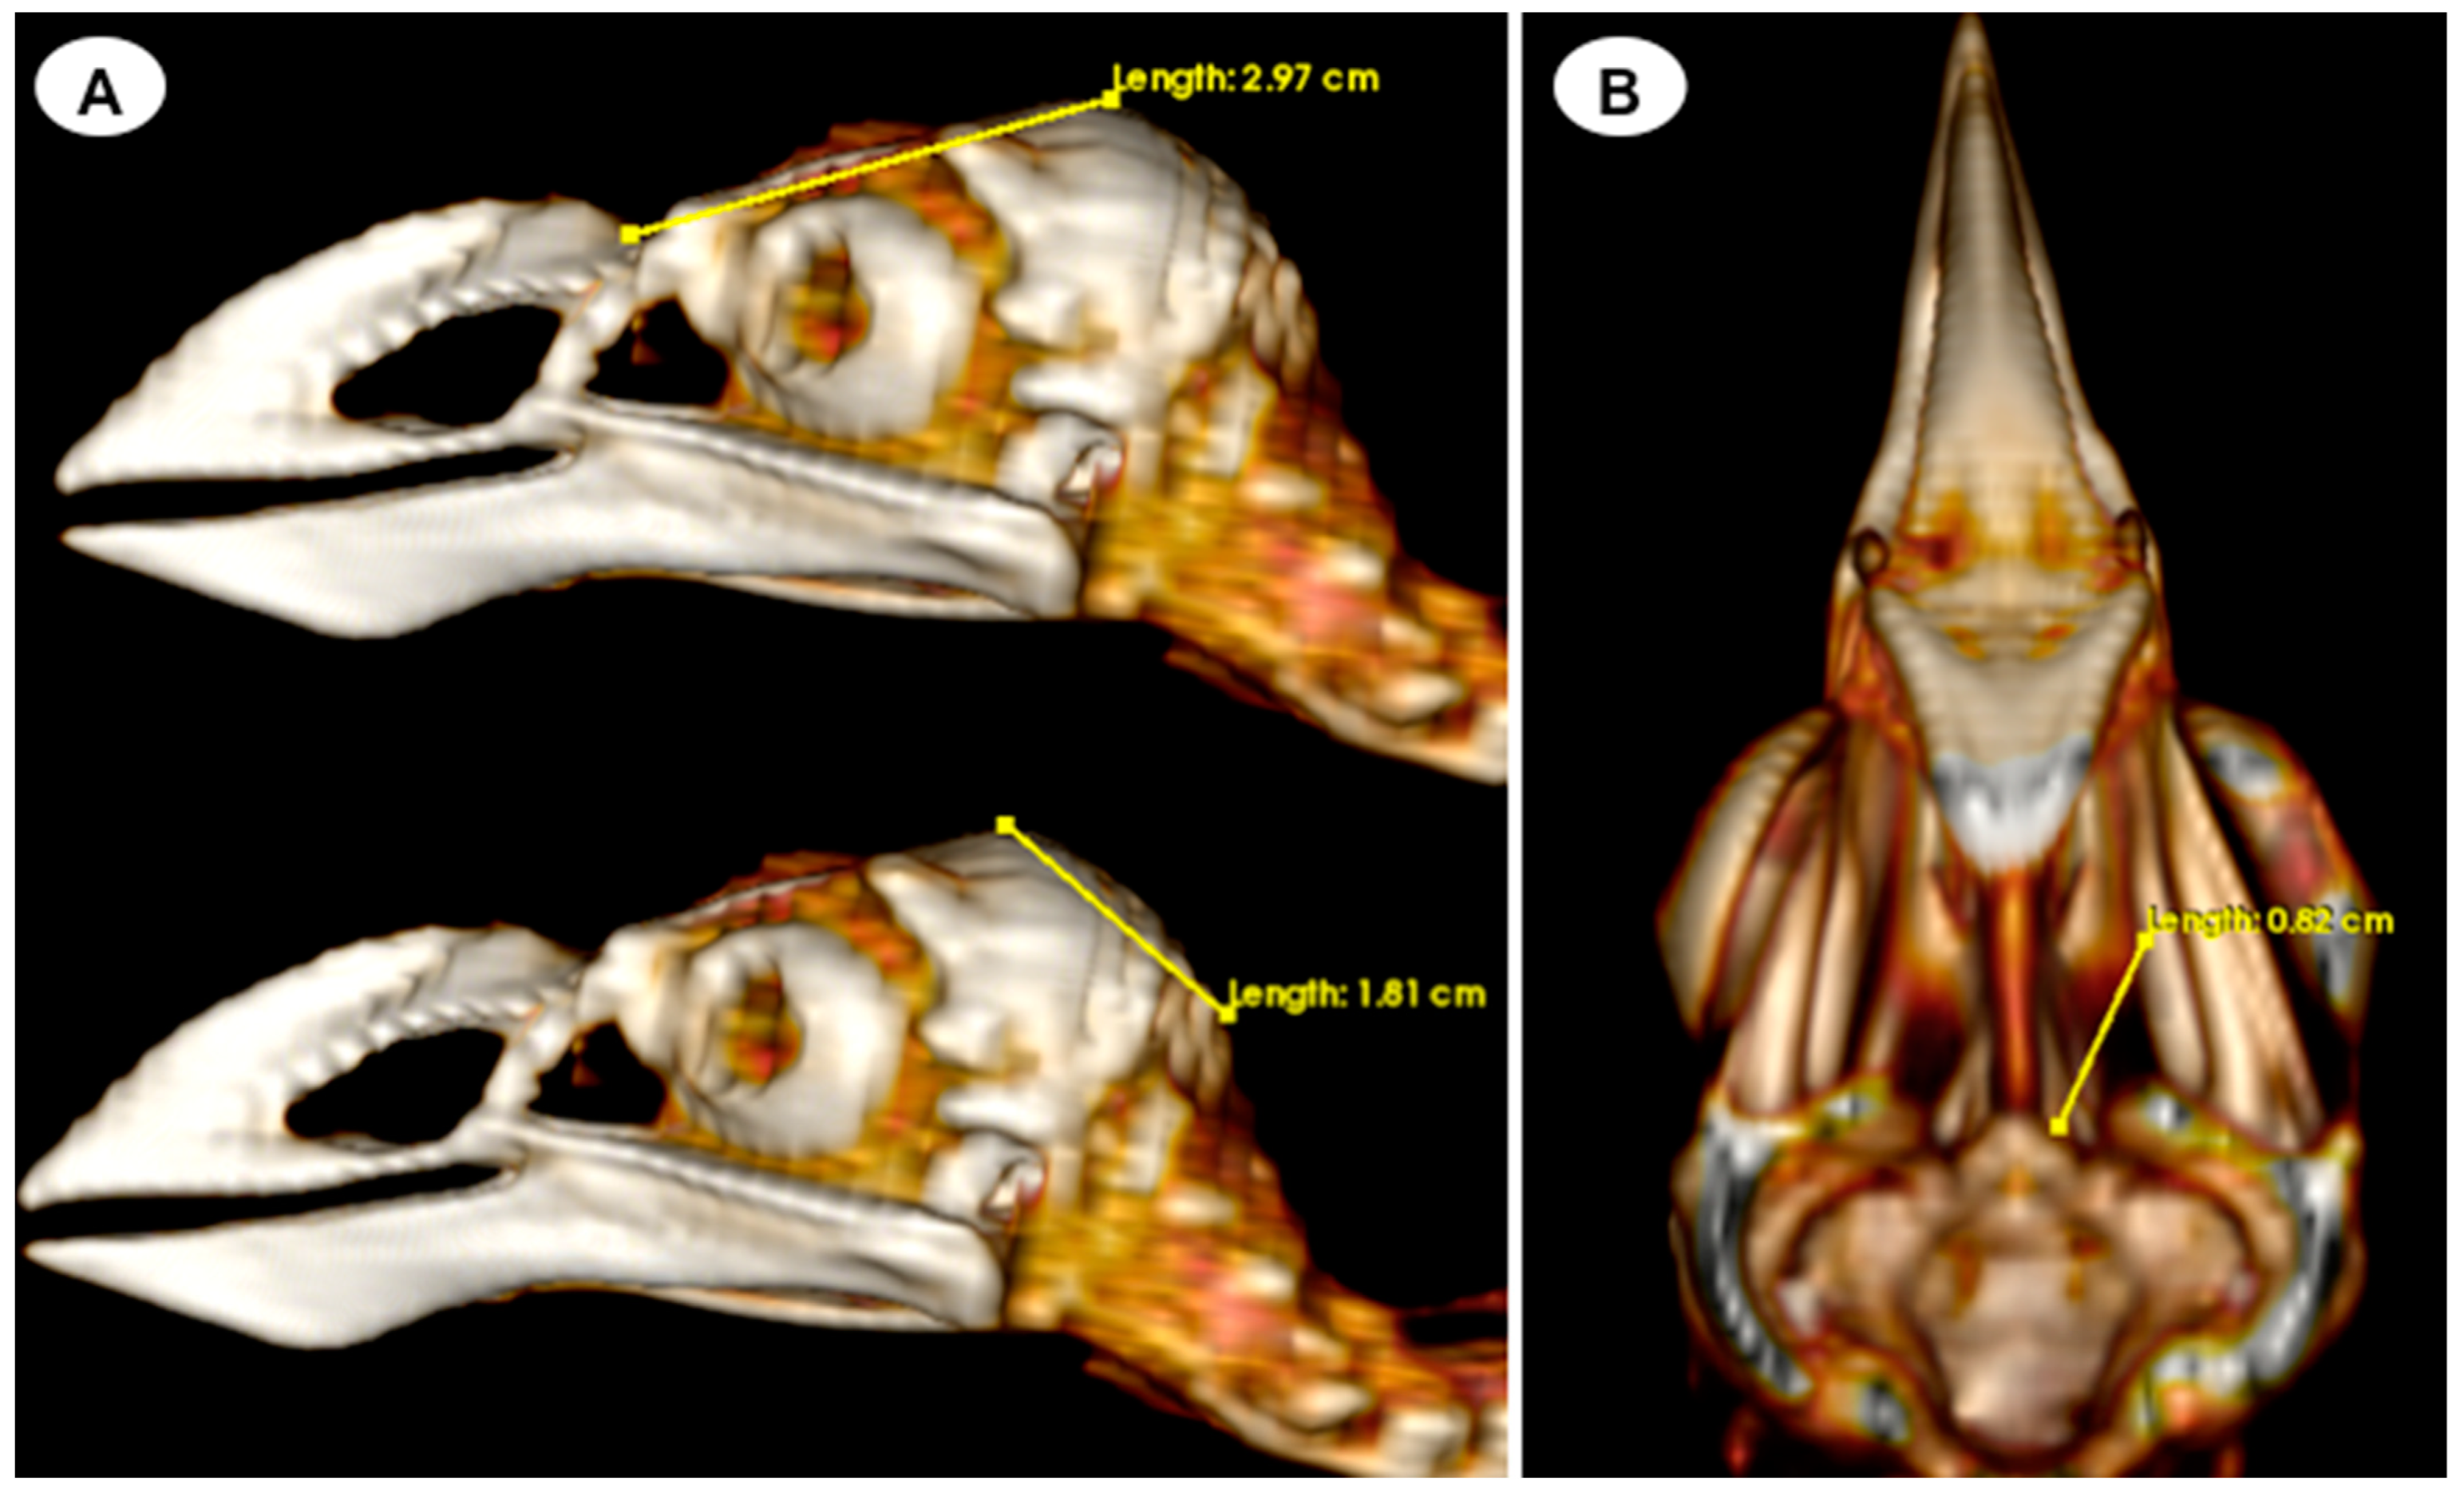

- Head length: This measurement is obtained from the centre point of the junction between the beak joint to the prominentia cerebellaris, providing the length of the head (Figure 5A);

- Depth of the orbit: This measurement represents the distance between the midpoint of the orbital diameter and the foramen opticum, indicating the depth of the orbit (Figure 5B).